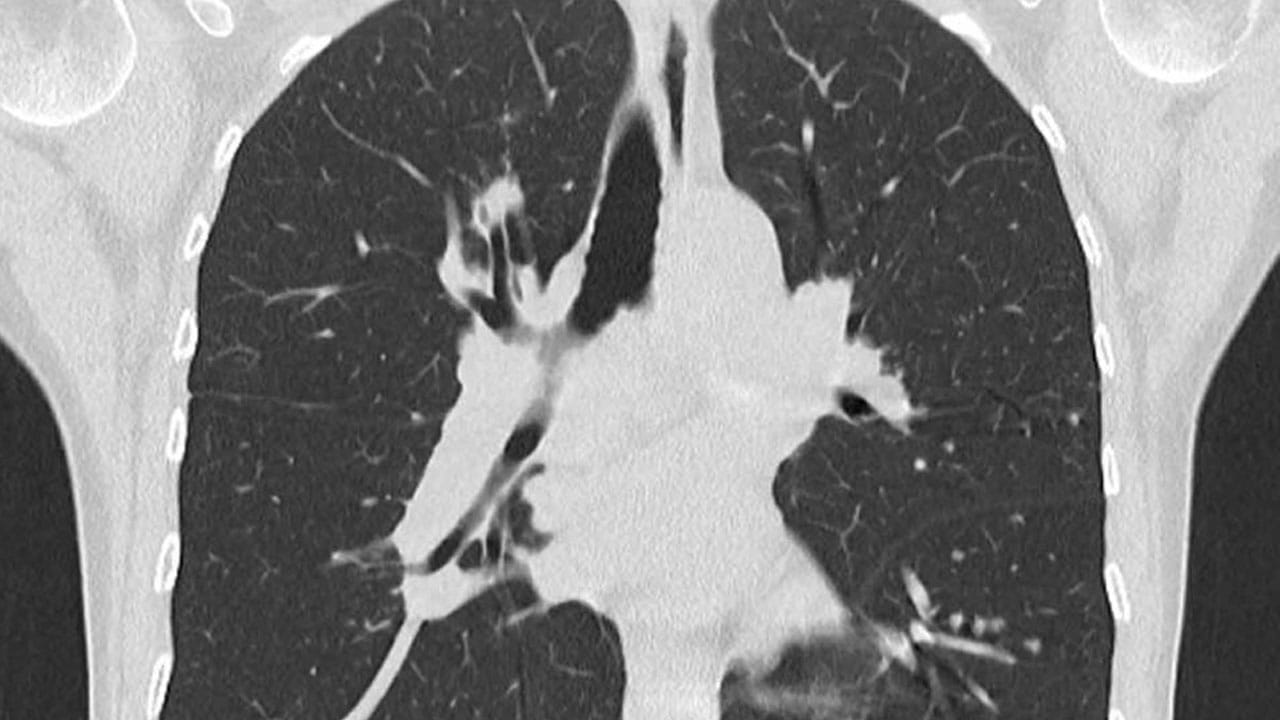

కరీంనగర్ ప్రాంతానికి చెందిన 26 ఏళ్ల యువకుడు.. తనకు ఐదేళ్ల వయసు ఉన్నప్పుడు ఆడుకుంటూ పెన్ క్యాప్ మింగేశాడు. గత నెల రోజుల నుంచి దగ్గు రావడం, బరువు తగ్గిపోవడం లాంటి లక్షణాలతో బాధపడుతున్నాడు. పది రోజులుగా దగ్గు విపరీతంగా పెరిగిపోయి, నిద్రపోవడానికి కూడా ఏమాత్రం వీలు కాకపోవడంతో వైద్యులకు చూపించగా.. సీటీ స్కాన్ తీయించారు. అప్పుడు ఛాతిలో ఎడమవైపు కిందిభాగంలో ఇన్ఫెక్షన్ ఉన్నట్లు తెలిసింది. దాంతో వాళ్లు హైదరాబాద్ పంపారు. ఇక్కడ కొండాపూర్ కిమ్స్ ఆస్పత్రిలో ఆ యువకుడికి సీటీ స్కాన్ చేసి, విషయం తెలుసుకుని దానికి చికిత్స చేసిన కన్సల్టెంట్ క్లినికల్, ఇంటర్వెన్షనల్ పల్మనాలజిస్ట్ డాక్టర్ శుభకర్ నాదెళ్ల ఇందుకు సంబంధించిన వివరాలు తెలిపారు.

“ఆ యువకుడు ఇక్కడకు వచ్చినప్పుడు ముందుగా సీటీ స్కాన్ చేశాం. అప్పుడు లోపల ఏదో ఒక గడ్డలా కనిపించింది. ఆ గడ్డ వల్లే ఊపిరితిత్తుల వద్ద ఆటంకం ఏర్పడి… దగ్గు వస్తోందని భావించాం. దాన్ని తీసేందుకు ప్రయత్నిస్తూ లోపల చూసేసరికి.. పెన్ క్యాప్ కనిపించింది. దాంతో ప్రొసీజర్ మధ్యలోనే ఆ యువకుడి అన్నను లోపలకు పిలిచి, గతంలో ఏమైనా మింగాడా అని అడిగాం. అప్పుడు.. ఐదేళ్ల వయసులో ఉండగా పెన్ క్యాప్ మింగేశాడని, అప్పట్లో తానే వైద్యుడి వద్దకు తీసుకెళ్తే అక్కడ పరీక్షించి లోపల ఏమీ లేదని.. బహుశా మలంతో పాటు వెళ్లిపోయి ఉండొచ్చని చెప్పారన్నాడు. దాంతో దాదాపు మూడు గంటల పాటు కష్టపడి, ఫ్లెక్సిబుల్ బ్రాంకోస్కొపీ సాయంతో ముందుగా దాని చుట్టూ పేరుకుపోయిన కణజాలాలు, లింఫ్నోడ్, కండలను కొద్దికొద్దిగా తొలగించాం. క్రమంగా అదంతా క్లియర్ అయిన తర్వాత అప్పుడు ఆ ప్లాస్టిక్ పెన్ క్యాప్ను కూడా బయటకు తీసేశాం. ఇన్ని సంవత్సరాల పాటు అలా ఒక ఫారిన్ బాడీ లోపల ఉండిపోవడం వల్ల ఊపిరితిత్తులు కూడా కొంత దెబ్బతిన్నాయి. అయితే, అక్కడ దెబ్బతిన్న ఇతర భాగాలను సరిచేసేందుకు యాంటీబయాటిక్స్ వాడాం. దాంతో అతను కోలుకున్నాడు.